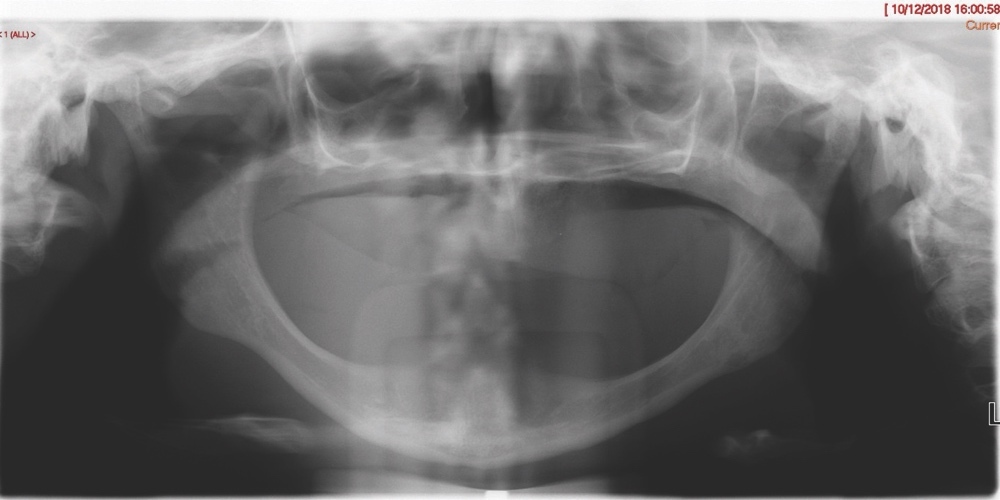

Upon clinical examination, she presented with a Class III skeletal pattern (Figure 1) with average vertical proportions, a hypoplastic maxilla, and she was edentate. She had undergone multiple previous attempts at denture construction; however, these were of limited success.

Intra-orally, the patient presented with an atrophic mandible and maxilla (Cawood and Howell13 Class VI and V, respectively) and was edentate (Figures 2 and 3). An orthopantomogram (Figure 4) confirmed the clinical findings and also demonstrated the proximity of the reduced maxillary ridge height to the maxillary sinuses.